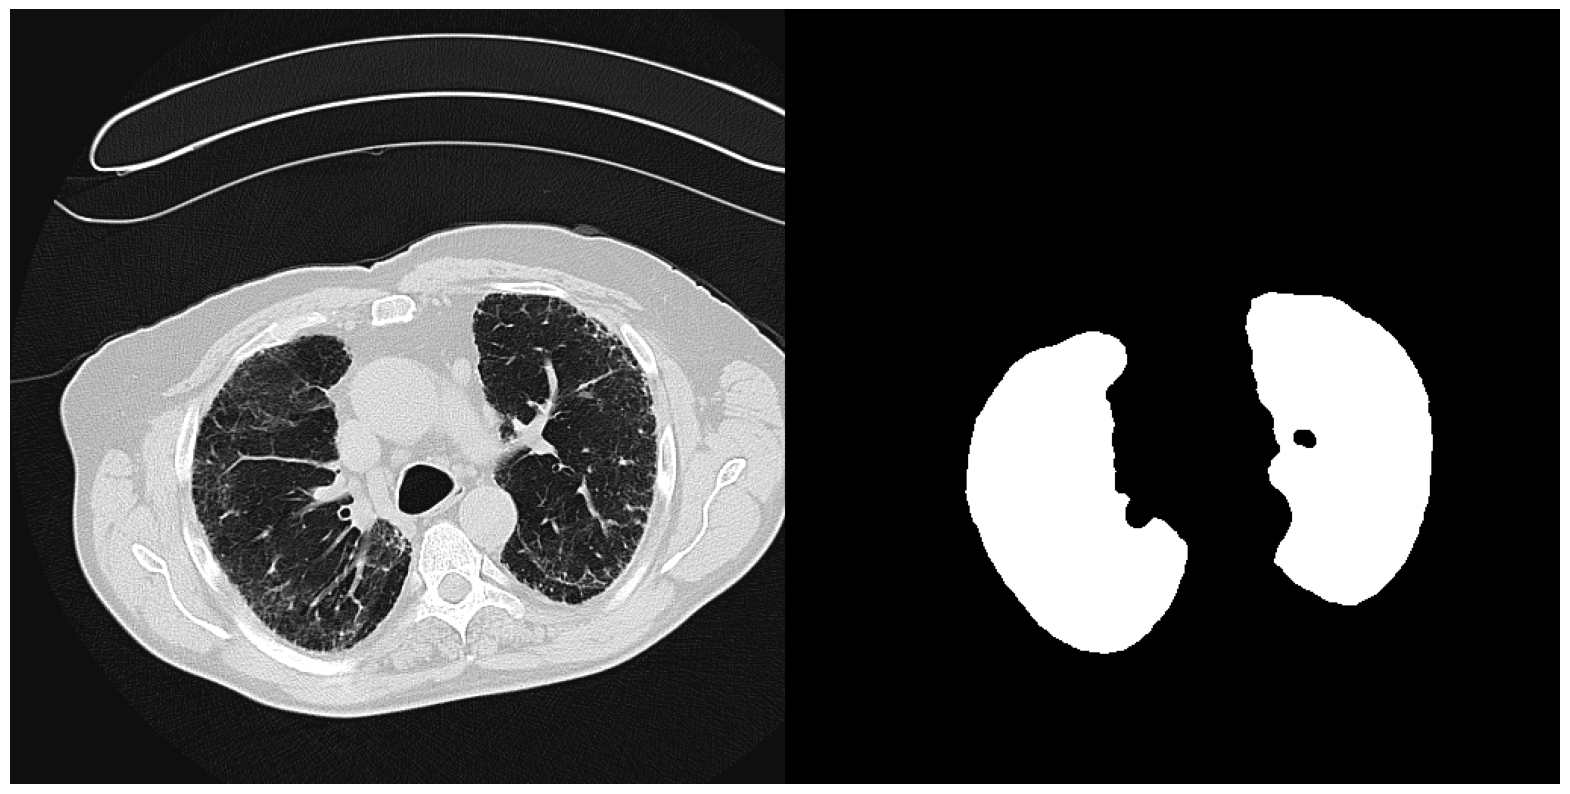

6.5.3 Validation with LUNG

The LUNG dataset is a collection of axial view lung CTs from three sources. The training and validation set consists of approximately 4000 slices extracted from 111 patient CT volumes from Pulmonary Fibrosis Progression (PFP), with their ground truth lung masks available in “CT Lung & Heart & Trachea segmentation” in Kaggle. We adopt another 90 axial view slices of lung CT volumes from “COVID-19 CT scans” showing lung with pneumonia as naturally occurring OOD data. (Access details in Section 4) The difference in the appearance of the COVID slices from the training set results not only from different imaging parameters but also from different infections. Each image is processed to have dimension 256×256256256256\times 256. We report below the mean IOUs and SBI of models trained on different models.

Training set IOUvalsubscriptIOU𝑣𝑎𝑙\mbox{IOU}_{val} IOUnoisysubscriptIOU𝑛𝑜𝑖𝑠𝑦\mbox{IOU}_{noisy} IOUOODsubscriptIOU𝑂𝑂𝐷\mbox{IOU}_{OOD} SBI

No Augmentation 0.982 0.938 0.962 2.650

Color Jitter 0.978 0.935 0.962 2.954

NST 0.978 0.941 0.962 3.014

Sep. Color Jitter 0.977 0.917 0.956 2.650

Negative Insertion 0.981 0.931 0.953 3.022

Random Resized Crop 0.942 0.793 0.853 2.534

Random Crop Reflect 0.979 0.672 0.943 2.128

Table 6: Performance of models trained on datasets with different augmentations when applied to the validation set, dataset with noise injected, and dataset with naturally occurred domain shifts for LUNG

Unlike in BFGT and FISH, as shown in Table 6, augmentations have much smaller effects on the performance of LUNG models. All augmentations that preserve targets’ shape yield models with very close performance on Validation, Noisy, and OOD data. Despite this, the effects of augmentations on SBI still align with our assumptions. Again, Random Resized Crop and Random Crop Reflect yield models with smaller SBI than the baseline, while the remaining augmentations increase each model’s SBI.

Refer to caption

(a) Image from "OSIC Pulmonary Fibrosis Progression" [38, 39]

(b) Image from "COVID-19 CT scans" [40, 41, 42]

(c) The image from "OSIC Pulmonary Fibrosis Progression" with (from left to right) Gaussian noise, shot noise, impulse noise, and defocus blur applied.

Figure 14: Samples from the three partitions of data domain in FISH

Augmentations, however, have negligible effects on this dataset. We explain this phenomenon by arguing that non-shape features may persist across multiple domains for LUNG. In LUNG, pixels associated with the lung have a texture style easily distinguishable from those associated with the rest of the image. The cooccurrence of high-intensity contours formed by cartilages also helps locate the lung. These features persist even across different image domains. In this case, the shape may not be the best discriminative feature in prediction capability. Non-shape features may be the more desirable feature sets to learn when optimizing the Cross-Entropy objective function. To avoid overstretching on interpreting the results, we will stop here with the conclusion that though Color Jitter and NST may suppress non-shape features, they barely hurt a model’s generalizability on Noisy and OOD data.